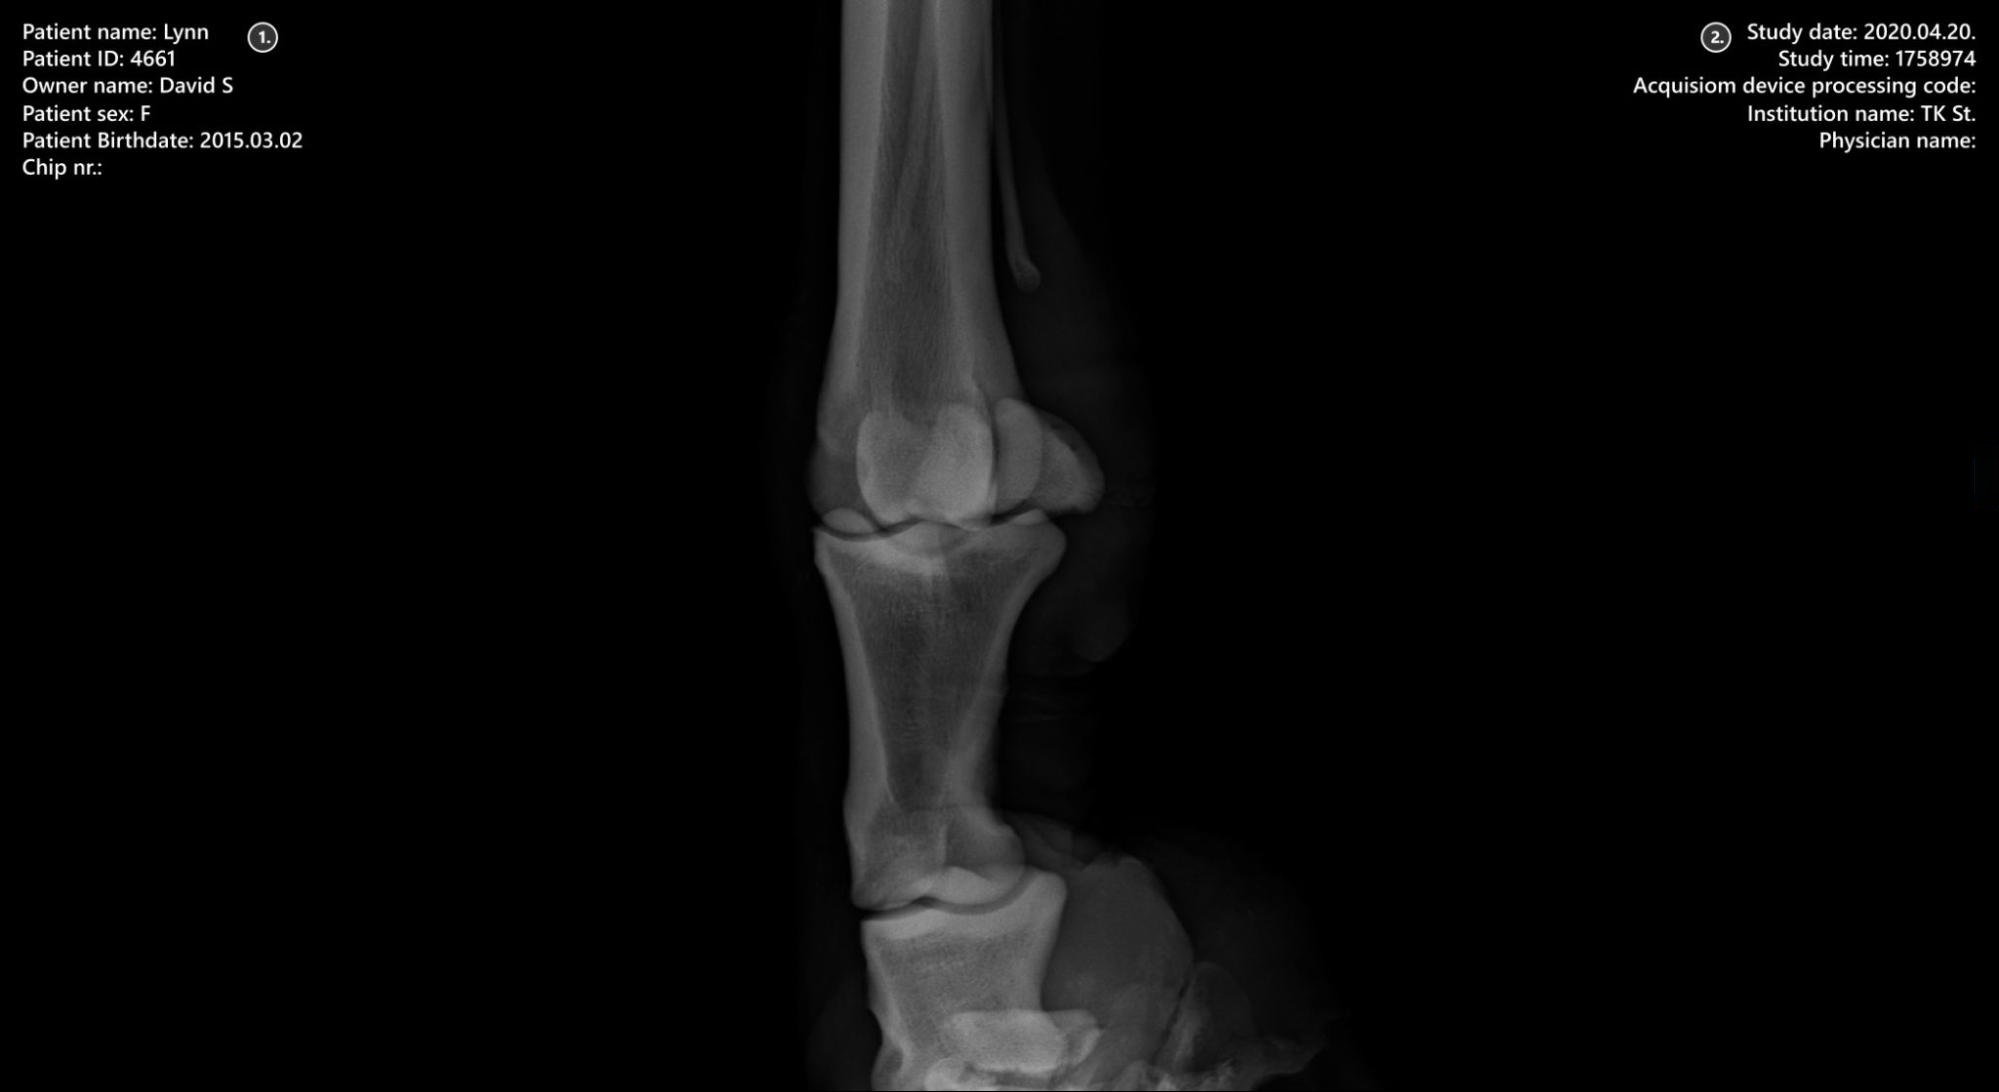

Viewer Area¶

Patient information

Study information